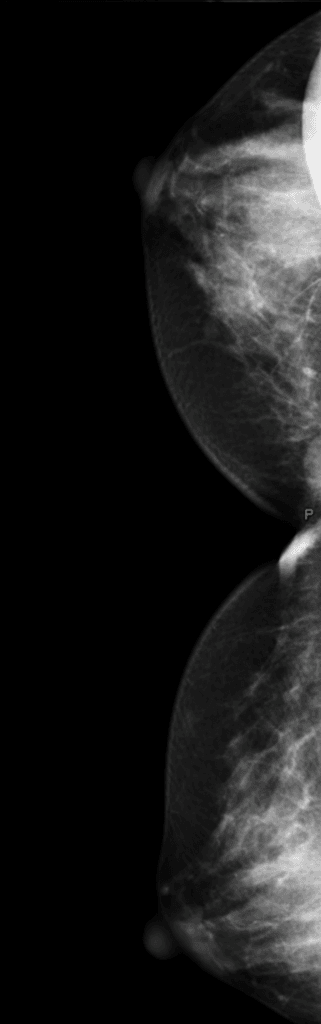

- Một khối choán chỗ (mass) giảm âm (hypoechoic), hình bầu dục (oval), giới hạn rõ (well-circumscribed), kích thước 23 x 10 mm với bờ dạng thùy nhẹ (slightly lobulated margins) và các dải tăng âm (echogenic strands) thưa thớt, nằm tại vị trí 10 giờ thuộc phần tư trên ngoài (UOQ).

- Tổn thương có hướng song song (parallel orientation) và biểu hiện chủ yếu là mềm trên siêu âm đàn hồi nén (strain elastography).

- Ghi nhận hai tổn thương khác có hình ảnh siêu âm tương tự nhưng kích thước nhỏ hơn tổn thương kể trên ở cả hai vú.

THẢO LUẬN (DISCUSSION): Xét thấy sự ổn định về kích thước của tổn thương đáng kể nhất giữa hai lần siêu âm vú cách nhau 6 tháng, cùng với hình ảnh siêu âm điển hình và các đặc điểm thăm khám lâm sàng (khối nhẵn, di động khi sờ nắn), gợi ý (suggestive of) một u xơ tuyến (fibroadenoma), phương án theo dõi bằng siêu âm hàng năm thay vì lấy mẫu mô (tissue sampling) đã được cân nhắc.

Thảo luận